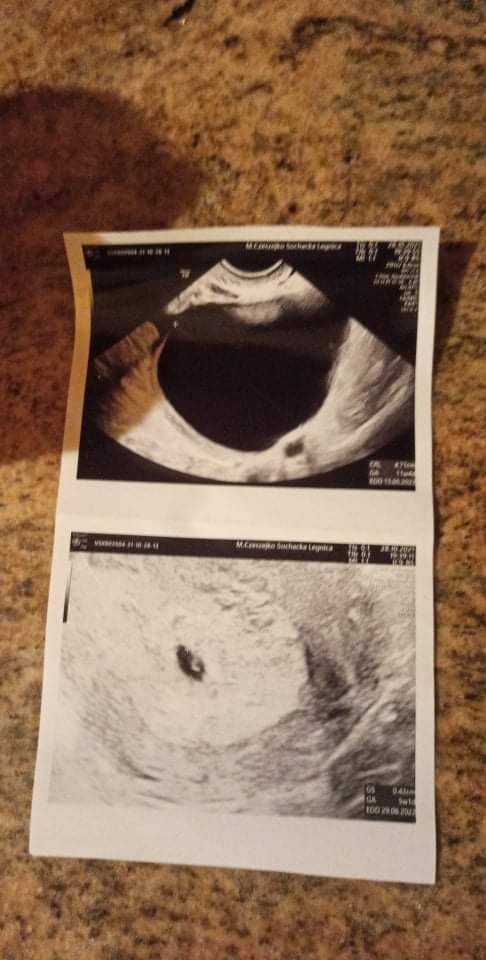

Cześć dziewczyny. U mnie dziś 7+6. Dzieci tak dają w kość, że wymieklismy z mezem totalnie. A wczoraj w końcu dostalam dokładne wymiary domu, który kupujemy i próbuje go zaprojektować, mam czas do jutra wieczora na rozrysowanie gdzie jakie sprzęty, gniazdka, rury z wodą i kanalizacja itp, bo w poniedzialek musi to architekt wrzucić na projekty i we wtorek maz zawiezie wykonawcom. Ja tego domu na oczy nie widziałam, bo sobie zaszłam w ciążę, a potem się okazało, że mam krwiaka, więc chyba dopiero za miesiąc, jak będzie przeprowadzka, to go zobaczę.